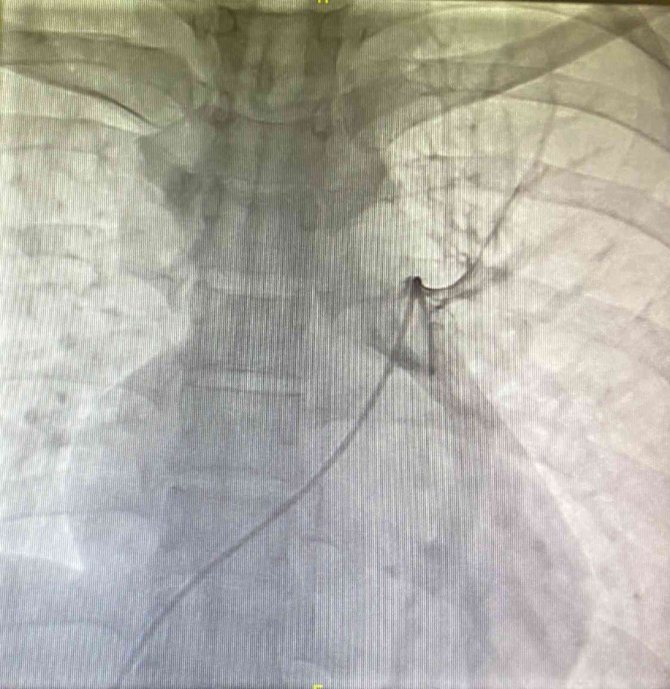

Manisa Şehir Hastanesi doktorları, geç kalındığında ölümcül sonuçlar doğuran akciğer pıhtısına anjiyografi yöntemiyle müdahale ederek, Manisa'da bir ilke imza attı. Otobüs yolculuğu sırasında baygınlık geçiren 3 çocuk annesi 36 yaşındaki Songül Ağdağ'a, Manisa Şehir Hastanesinde akciğere pıhtı atması (masif pulmoner emboli) tanısı konuldu. Hemen hastanenin başhekim yardımcısı ve aynı zamanda göğüs hastalıkları hekimi Uzm. Dr. Önder Utku Datlı ve kardiyoloji hekimi Uzm. Dr. Mehmet Burak Özen bir araya gelerek, hastaya anjiyografi yöntemiyle tedavi uygulamaya karar verdi. Uzm. Dr. Mehmet Burak Özen tarafından hastaya iki akıllı kateter yerleştirilerek ultrasonik (ses dalgaları) tromboliz (pıhtı eritilmesi) işlemi gerçekleştirilerek, akciğer içinde oluşan pıhtı tamamen eritildi ve hastanın hayatta kalması sağlandı. Yapılan operasyonla ilgili bilgi veren Manisa Şehir Hastanesi Başhekim Yardımcısı ve Göğüs Hastalıkları Hekimi Uzm Dr. Önder Utku Datlı, "Bir yıl önce Covid hastalığı geçirip akciğere pıhtı atması şikayetiyle bize başvuran hasta, 35 yaşında genç bir hasta olması sebebiyle tarafımızca değerlendirildi ve bu pıhtı atmasının ölümcül masif emboli olduğu saptandı. Kardiyoloji ile birlikte hastamıza gerekli tedaviyi uyguladık. Pulmoner artere kateter ile girerek, bu tedaviyi yaptık. Bu işlemde kardiyoloji doktorumuz Burak bey anjiyoda bize yardımcı oldu. Bu işlem sayesinde hasta, hayati tehlikesini atlatmış oldu" dedi.

Covid hastalığına bağlı olarak akciğere, beyine, kalbe pıhtı atışlarında belirgin artışlar saptandığını tespit ettiklerini de vurgulayan Datlı, "Bununla ilgili çok sık vakalarımız olmaya başladı ama genç hastalardaki bu pıhtı atışı çok daha tehlikeli olmakta. Akciğerdeki pıhtı atmaları da çok ölümcül seyretmekte. Bu hastamızda da her iki akciğerini besleyen iki ana damarında pıhtı attığı için gerekli tedaviyi lokal pulmoner arter kateteri uygulayarak yaptık" diye konuştu.

Anjiyografi yöntemiyle tedaviyi uygulayan Manisa Şehir Hastanesi Kardiyoloji Hekimi Uzm. Dr. Mehmet Burak Özen de son zamanlarda akciğere pıhtı atma vakalarında ciddi artışlar yaşandığına dikkat çekerek, "Akciğere pıhtı atma olayı bir kalp krizi gibi, bir felç gibi ani müdahale edilmesi gereken bir olay. Genç hastalarımızda bunu son zamanlarda çok daha sık görmekteyiz. Bu hastamızda akciğer atar damarının büyüklüğü nedeniyle her iki ana damarda bir su bardağı kadar pıhtı vardı. Hastayı göğüs uzmanımız değerlendirdi, acil müdahale kararı aldık. Bu hastalarda önemli olan pıhtı eritici tedavi vermek ama bu pıhtı eritici tedaviyi damar yoluyla uyguladığımızda çok ciddi yan etkileri olabiliyor bazen. Hem bu yan etkileri azaltmak hem de tedavinin etkisini arttırmak için hastanın kasık toplar damarından girerek, oradan iki kateter vasıtasıyla hastanın her iki akciğer atar damarına ulaştık. Buradaki kateterler hem pıhtı eritici ilacı direkt pıhtı içine salarak etki edecek hem de kateterin özelliği olarak bu pıhtı tıkacını ultrasonik dalgalar ile dağıtılmasını sağlayacaktı. Bu kateterlerle hastamıza özel 24 saat pıhtı eritici tedaviyi ve ultrasonik pıhtı dağıtmasını uyguladık ve hastamız bu tedaviden çok büyük fayda gördü. Bu tedavi başarılı olarak Manisa'da ilk defa hastanemizde uygulandı. Tedaviyi göğüs hastalıkları uzmanımız ile birlikte anjiyografi yöntemiyle uyguluyoruz. Artık göğüs uzmanlarımız ile birlikte anjiyografi yöntemiyle pulmoner artere atan pıhtılara bu şekilde müdahale edeceğiz. Hastamızın durumu gayet iyi" diye konuştu.